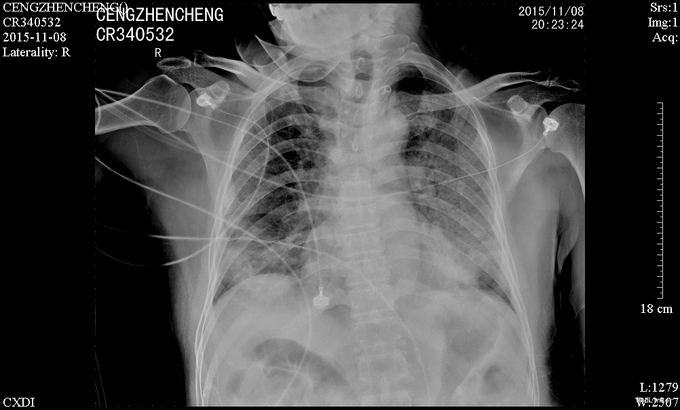

患者诉仍有咳嗽咳痰、呼吸困难、胸闷气促,咳白色粘痰,平卧及活动时加重,坐起后缓解,无发热,无咯血,精神、睡眠一般,饮食欠佳,大小便正常。高流量吸氧(7L/min)下血氧饱和度维持在93-95%,心率65-75次/分。查体:神志清楚,查体合作,胸廓未见异常;双肺呼吸音粗,双侧肺可闻及少许细湿罗音,无胸膜摩擦音;心界不大,心律齐,各瓣膜听诊区未闻及病理性杂音;腹平坦,无压痛、反跳痛,肝脏肋下未触及。辅助检查:感染三项:降钙素原(ProCT)6.00ng/ml;淀粉样蛋白A(SAA)281.8mg/L;C反应蛋白(CRP)。真菌D-葡聚糖(1_2_3βD)315pg/mL。巨细胞病毒定量(FQ_HCMV)2.85E+3copies/m。凝血功能:血浆D-二聚体测定(D-Dimer)0.85mg/L FEU;活化部分凝血活酶时间(APTT)46.8秒;血浆凝血酶原时间测定(PT)14.0秒。肾功能:尿素(BUN)19.52mmol/L;肌酐(CR)223μmol/L。肝功能:丙氨酸氨基转移酶(ALT)79U/L;天门冬氨酸氨基转移酶(AST)60U/L;总蛋白(TP)54.3g/L;白蛋白(ALB)21.8g/L150.67mg/L。前-脑利尿肽(Pro-BNP)572.1pg/mL。胸片示:1、两肺炎症,较前进展,建议治疗后复查;2、主动脉硬化;3、左肾区致密影,请结合临床其他检查;4、右第4肋骨陈旧骨折。

诊断:1.重症肺炎 2.I型呼吸衰竭 3.肾移植术后慢性肾功能不全 4.左肾结石 5.同种异体肾移植术后 6.药物性免疫缺陷病 治疗:予更昔洛韦抗病毒、百炎净+亚胺培南西司他丁+莫西沙星抗细菌、免疫球蛋白冲击等抗感染治疗,注意根据患者肌酐清除率计算药物剂量,定期监测感染指标,调整抗感染方案;2、患者免疫抑制过程中出现感染,需降低免疫抑制强度,予甲强龙(80mg 1/日)、普乐可复(1.5mg 1/早,1.0mg 1/晚)、米芙(180mg 2/日)、五酯胶囊抑制免疫力;3、患者白蛋白较低,注意补充;4、注意护肝、降糖、碱化尿液等对症处理。2日后呼吸困难没有改善,查D葡聚糖315pg/mL,不排除真菌感染,加用科赛斯抗真菌治疗,持续20天后患者呼吸困难好转,血常规及CRP等值恢复正常